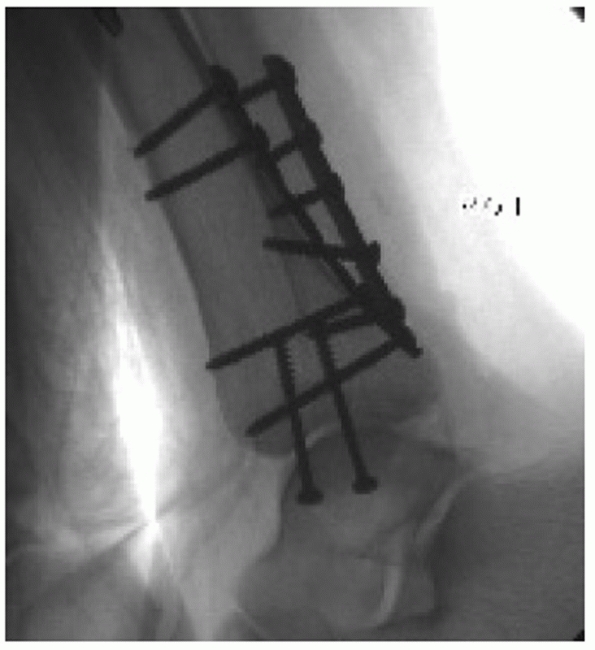

![]() |

FIGURE 57-3 Radiographic appearance of the normal ankle on mortise view. A. The condensed subchondral bone should form a continuous line around the talus. B.

Talocrural angle should be approximately 83 degrees. When the opposite side can be used as a control, the talocrural angle of the injured side should be within a few degrees of the noninjured side. C. The medial clear space should be equal to the superior clear space between the talus and the distal tibia and less than or equal to 4 mm on standard radiographs. D. The distance between the medial wall of the fibula and the incisural surface of the tibia, the tibiofibular clear space, should be less than 6 mm. |

FIGURE 57-4 A.

The “ball” or “dime sign” is described on the AP view as an unbroken curve connecting the recess in the distal tip of the fibula and the lateral process of the talus when the fibula is out to length. B. Fibula malreduced in a shortened position, ball sign is absent. |